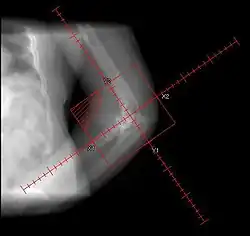

• Randomized. 161 patients. Preop RT 7/1 (<4 hours) vs. Postop RT 17.5/5 (<=96 hours). Portals periacetabular and intertrochanteric soft tissues

• Randomized. 249 patients, high risk. Post-op RT 10/5 vs. 17.5/5. Portals periacetabular and intertrochanteric soft tissues

• Randomized, multi-institutional. 98/122 patients with risk factors, following elective hip replacement. Treated with pre-op RT 7-8/1 <4 hours vs. post-op RT 7-8/1 <48 hours. Fields to soft tissues between periacetabular region of pelvis and intertrochanteric portion of femur. Median F/U 9.5 months

• Randomized. 62 hips in 55 patients at high risk. Treated with postop RT 8/1 vs. 10/5 limited field (includes lateral aspect of greater trochanter). Minimum F/U 6 months